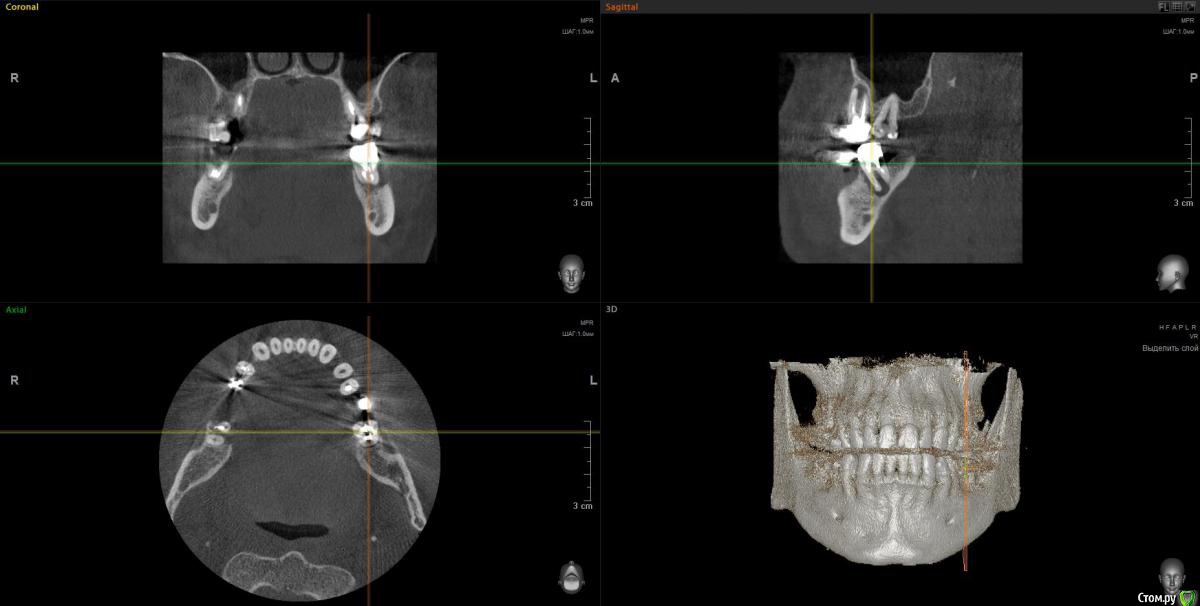

wladdX Опубликовано 12 февраля, 2018 Поделиться Опубликовано 12 февраля, 2018 Скрины 1 Ссылка на комментарий

Taurus007 Опубликовано 13 февраля, 2018 Автор Поделиться Опубликовано 13 февраля, 2018 wladdXОгромное спасибо за скриншоты. Я бы даже близко так не смог) Пришел расчет и анализ ТРГ. Заключение.pdf Ссылка на комментарий

Bier Опубликовано 22 февраля, 2018 Поделиться Опубликовано 22 февраля, 2018 Справа синуслифтинг не потребуется 100%Слева - возможно в области 26 зуба. Для оценки прикуса одного ТРГ мало, надо еще фото моделей. Вам их наверное делали? Ссылка на комментарий

Taurus007 Опубликовано 24 февраля, 2018 Автор Поделиться Опубликовано 24 февраля, 2018 Справа синуслифтинг не потребуется 100% Слева - возможно в области 26 зуба. А в целом, можно ли сейчас не трогать область, где возможно потребуется синуслифтинг, поскольку в практическом смысле это наименее проблемная область, хоть коронки и стоят уже 9 лет ? надо еще фото моделей. Вам их наверное делали? Не делали. Это как-то в домашних условиях возможно? Ссылка на комментарий